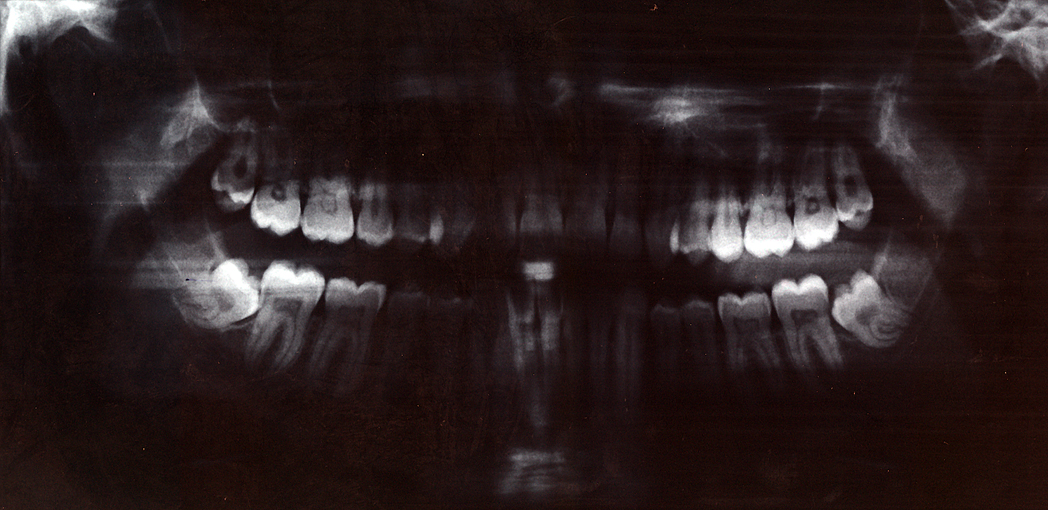

Orthopantomogram (OPG) phantom showing full mandible and maxilla with all teeth, TMJ, sinuses, and surrounding anatomy

Dental phantom showing common pathology: carious lesions, periapical abscess, root resorption, and a metallic restoration